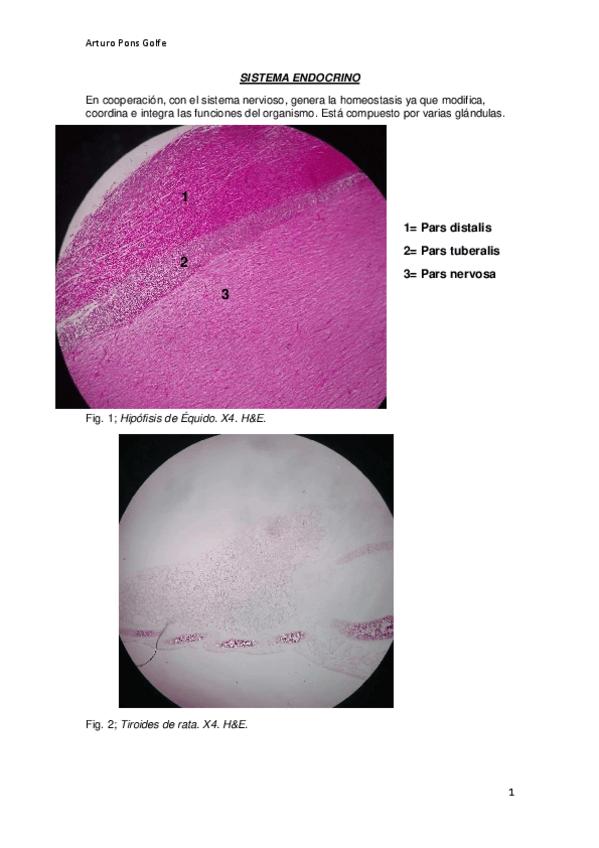

SISTEMA-ENDOCRINO-Y-AP.pdf